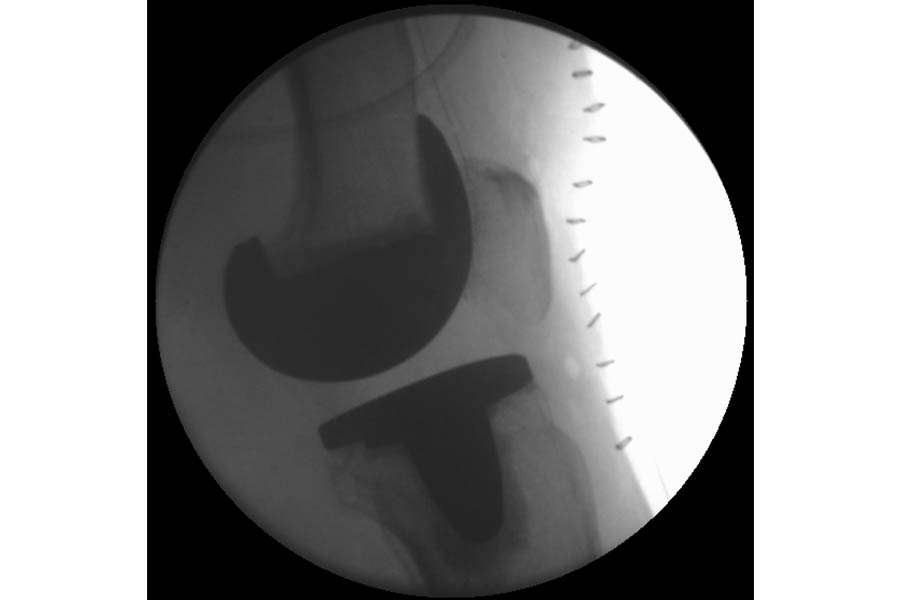

Total Knee Replacement

Case 1